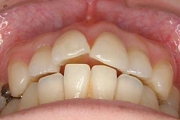

☆審美ワイヤー(光拡散型)の使用例と

ホワイトワイヤー(コーティング)での治療例

審美ホワイトワイヤー

光拡散ロジウムコートtypeワイヤー

ゴールドシリーズ審美ワイヤー

ホワイトコーティングtypeワイヤー